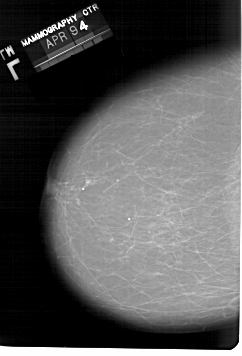

A_1331_1.RIGHT_MLO

RIGHT_MLO LINES 6826 PIXELS_PER_LINE 4591 BITS_PER_PIXEL 12 RESOLUTION 43.5 OVERLAY

FILE: A_1331_1.RIGHT_CC.OVERLAY

TOTAL_ABNORMALITIES 1

ABNORMALITY 1

LESION_TYPE CALCIFICATION TYPE PLEOMORPHIC DISTRIBUTION CLUSTERED

ASSESSMENT 4

SUBTLETY 1

PATHOLOGY BENIGN

TOTAL_OUTLINES 1

BOUNDARY